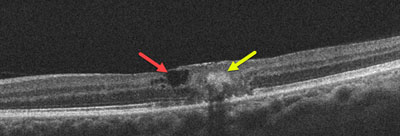

Macular telangiectasia is detected during a dilated ocular examination. Macular changes include retinal pigment clumps, inner retinal crystals, and a whitish retinal discoloration. OCT scanning and fluorescein angiography are often used to confirm the diagnosis. Patients are often misdiagnosed as having age-related macular degeneration since the findings can appear somewhat similar.